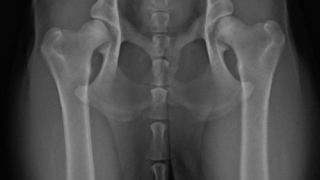

Developmental Orthopedic Diseases (DOD) are the most common cause of lameness in growing dogs. Examples of DODs include: Hip and Elbow Dysplasia Osteochondrosis/ Osteochondritis Dissecans (OC/OCD) Avascular Necrosis of the Femoral Head Patellar Luxation All of these conditions affect the […]